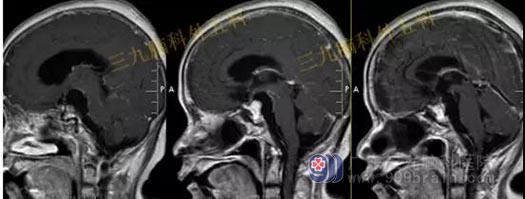

头部MR检查提示:鞍区短T1稍短T2异常信号影,大小约8mm×10mm×10mm,垂体受压下移,垂体柄受压后移。视交叉轻度受压上抬。鞍区异常信号影,考虑Rathke's囊肿可能性大。

手术过程:完善相关检查后行内镜经鼻蝶鞍区Rathke’s囊肿切除术,通过微创全切囊肿。

术后MR检查提示:经鼻蝶鞍区占位性病变切除术后改变,原病变已切除。